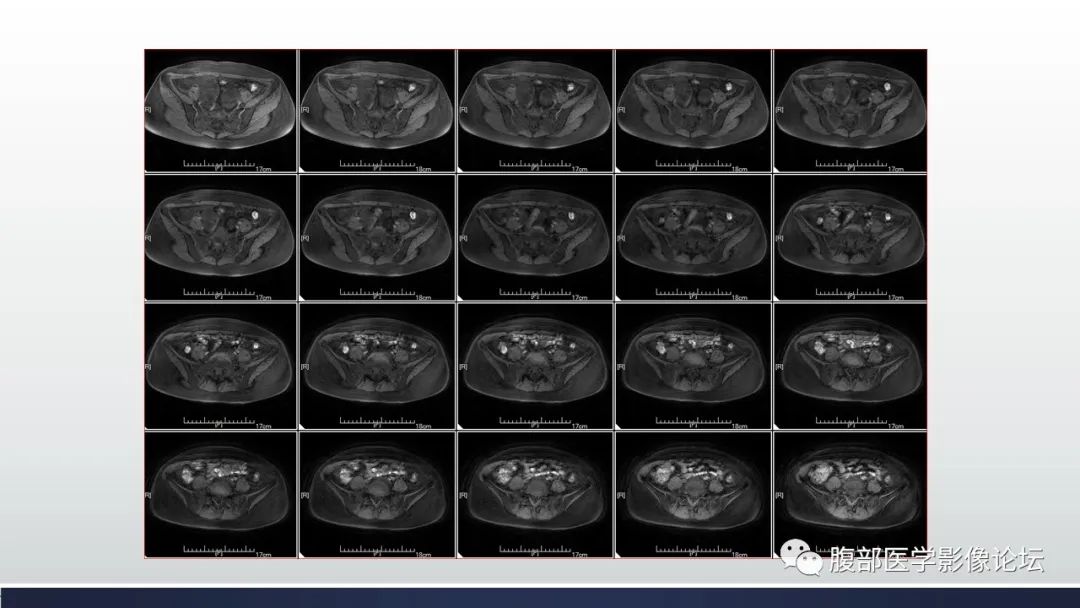

【病例】子宫内膜透明细胞癌1例MR-13

【病例】子宫内膜透明细胞癌1例MR-14

【病例】子宫内膜透明细胞癌1例MR-15

【病例】子宫内膜透明细胞癌1例MR-16